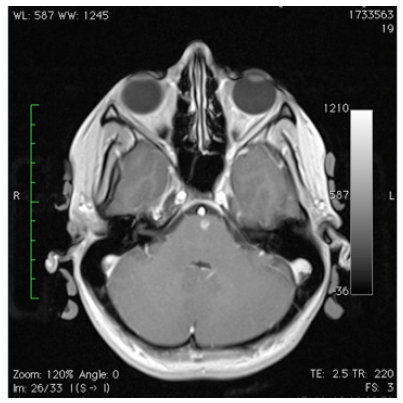

The mother and grandmother had also frequent nosebleeds with the presence of telangiectesia at the levels of the lips, tong, fingers and stomach. These findings were absent in our presented patient. The magnetic resonance (MR) angiography of the brain showed no arteriovenous malformations (Figure 1). On MR imaging a small bleed was observed in the right superior colliculus at the level of the mesencephalon (Figure 2). Also a small bleed was detected in the left anterior paramedian part of the pons (Figure 3).

Figure 2 Magnetic resonance imaging of a horizontal section at the level of the mesencephalon. Note the presence of a small haemorrhage in the right colliculus superioris.